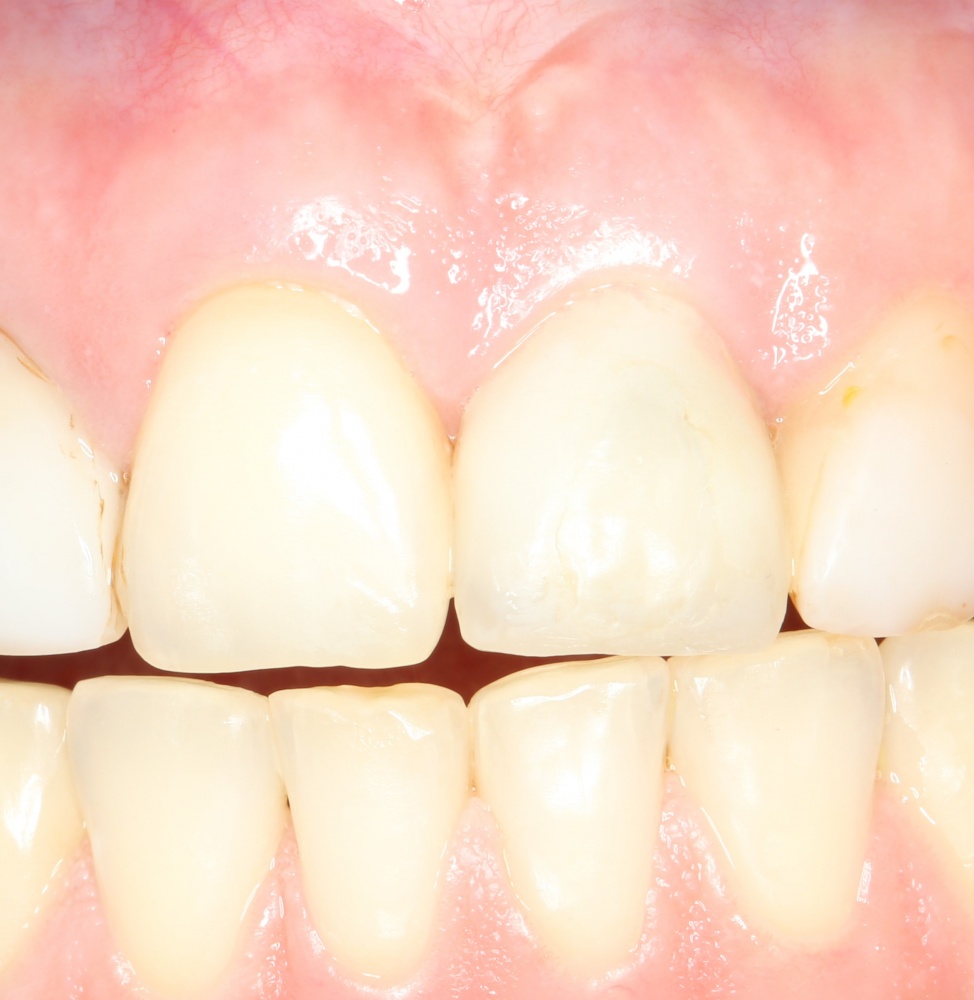

Рекомендации по установке имплантов. Для всех. Часть V.